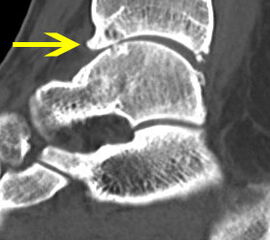

Abbildung 13-14, Video 7

Osteochondrale Läsion an der rechten medialen Talusschulter. Die Knorpelfläche erscheint bei der initialen Inspektion häufig intakt, erweist sich dann bei der Tasthakenpalpation allerdings als deutlich weicher verglichen mit dem umliegenden intakten Knorpelgewebe. In den meisten Fällen lässt sich mit dem Tasthaken ein Riss in der Oberfläche nachweisen und eine lose chondrale bzw. osteochondrale Schuppe abheben. Die instabilen Knorpelanteile und die sklerotisch veränderten Anteile der subchondralen Knochenschicht müssen mit einer Kürette oder einem Shaver entfernt werden, bis ein stabiler Rand aus gesundem Knorpelgewebe besteht. Die Eröffnung des subchondralen Knochens erfolgt mit einer gebogenen Ahle. Anschließend (ggf. nach dem Öffnen der Blutsperre) sollten kleine Blutungen aus den Knochenkanälen erkennbar sein.